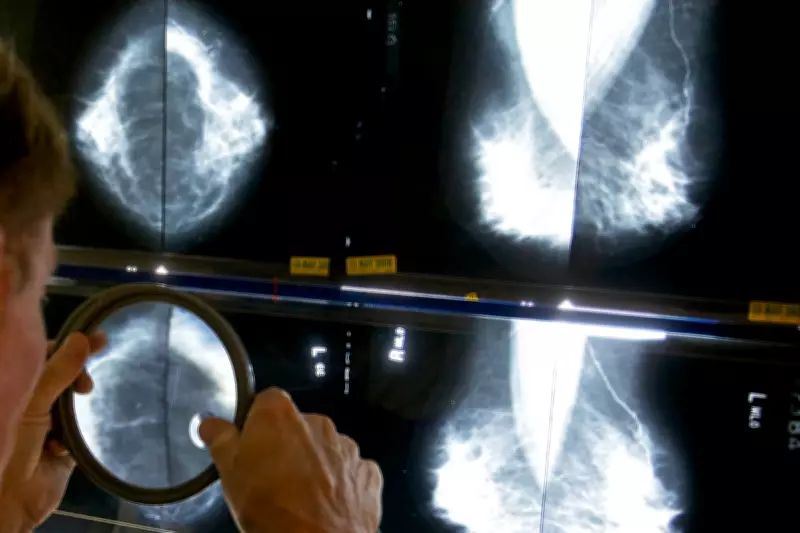

Implications for Breast and Ovarian Cancer

One of the most promising findings suggests that significantly more breast and ovarian cancer patients could benefit from targeted therapies such as PARP inhibitors. This is due to the identification of homologous recombination deficiency (HRD) in a higher percentage of tumours than previously estimated. HRD is a key biomarker that makes cancers more susceptible to certain treatments, and its broader detection could expand access to effective therapies for many patients.